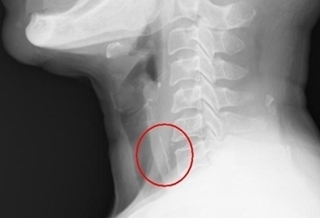

(優活健康網新聞部/綜合報導)苗栗一名2歲的女童因誤吞父母的戒指,至醫院急診就醫,經X光檢查發現戒指已掉到胃部,需進行無痛胃鏡才能取出。由於女童空腹時間不足,胃部可能還有殘留食物,因此經麻醉醫師審慎評估後,採取全身麻醉,並置入氣管插管,保護呼吸道以防嗆入嘔吐物,經過多次以胃鏡進出,分批將胃中食物殘渣撈出,終於順利將誤吞的戒指取出。1歲半前口腔期 寶寶會透過嘴巴探索世界大千綜合醫院肝膽腸胃科醫師林裕鈞表示,誤吞異物時建議於6至24小時內接受胃鏡取出的物品,包含尖銳物、電池、磁鐵、毒藥物、或超過2.5公分的鈍狀物,此次女童誤吞的戒指屬於鈍狀物,但直徑將近2公分,對幼兒來說相對較大。由於6個月至4歲的小朋友很容易誤食異物,尤其是6個月到1歲半前的口腔期,寶寶會通過嘴巴的咀嚼與味覺來探索、認識世界,並透過吃和將東西放到口中,來獲得滿足,所以會不斷嘗試抓東西往嘴裡塞,大人一定要特別留意。就醫前不要催吐或喝醋 以免造成二次傷害如果不小心發生誤吞異物,家長應先保持鎮靜,了解誤吞物品的形狀、大小與數量,就醫前不要用吞飯、催吐、喝醋等方式處理,以免造成二次傷害,同時也確保如需緊急做胃鏡或手術時,可以維持空腹6至8小時以上。若出現呼吸困難、無法出聲,表示異物梗塞氣管,應馬上撥打119,並執行哈姆立克法直到異物咳出或嘔出。想要預防嬰幼兒誤吞異物,林裕鈞醫師建議,可以選擇符合年紀的安全玩具,將家中藥品、硬幣等容易誤吞的物品放置高處或鎖在櫃子裡,幼兒哭泣時應避免餵食,若有帶骨、刺、核的食物與硬質糖果,也不建議給學齡前幼童自行食用。另外,民眾就醫希望接受胃鏡檢查摘除異物,並非馬上就能施作。小魚刺雞骨多會軟化溶解 不一定要做胃鏡若空腹時間不足8小時,可能會因為檢查過程嘔吐併發吸入性肺炎,也因為食物殘渣的遮掩,增加尋找和撈取異物的困難度。此外,較小的魚刺雞骨,約80%都會自行滑入胃中軟化溶解,喉頭的異物感經過3至5天會逐漸緩解,若沒有吞嚥困難、吞嚥疼痛等警示症狀,不一定有急做胃鏡的必要性。